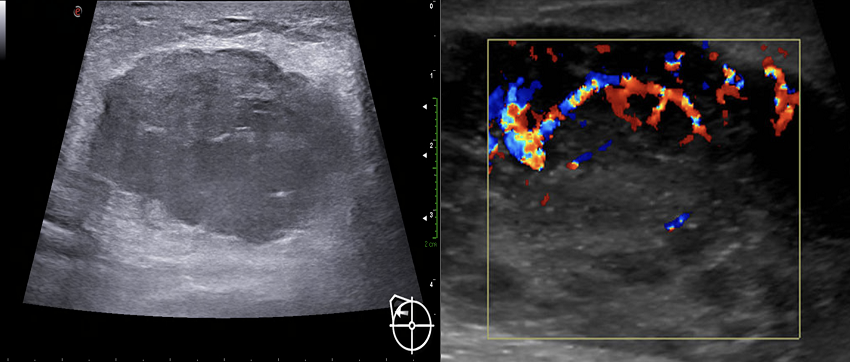

El estudio se complementó con ecografía mamaria (Figura 2), la cual reportó tejido mamario fibroglandular y heterogéneo, con distorsión de la arquitectura, con un tumor en glándula mamaria derecha en el radio de la 1, bordes microlobulados y heterogéneos debido a zonas de mayor y menor ecogenicidad en el interior, sin reforzamiento posterior, con vascularidad interna incrementada a la aplicación de Doppler color. Los complejos areola-pezón con ductos de calibre y distribución adecuados. A nivel cutáneo se apreció engrosamiento de la piel. En las axilas se reportaron ganglios de tamaño y forma adecuadas, que conservaban su centro graso.

Una vez integrados los estudios de imagen se otorgó una categoría Breast Imaging Reporting and Data System (BI-RADS) 5, según el sistema del American College of Radiology, por lo que se prosiguió a realizar biopsia con aguja gruesa guiada por ultrasonido para su estudio histopatológico.